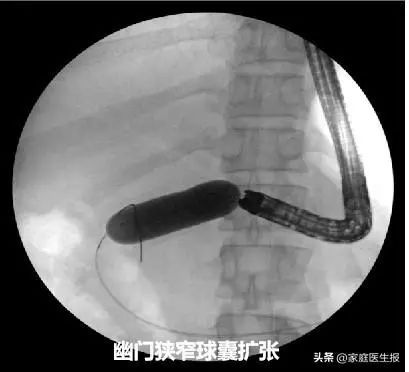

术中,熊光苏带领团队首先通过球囊扩张狭窄变形幽门部,进入十二指肠球部发现肿瘤已浸润导致管腔狭窄。直视下运用取石球囊带导丝越过狭窄段,注入造影剂肠腔显影,球囊打开后回拉至狭窄处,明确狭窄段长度。X光引导下成功置入长度60mm、直径26mm的金属支架,整个过程仅耗时15分钟。

熊光苏又补充道:“这例患者还算比较顺利的,我们放置十二指肠支架后能顺利到达降部。以往有的患者因为压迫严重,放置十二指肠支架后内镜还是无法通过,往往需要临时再次球囊扩张保证内镜通行。支架置入的同时,往往又会影响乳头的观察,因为操作空间和视野狭小,寻找乳头及后续ERCP操作非常不顺手。部分情况下,为了保证手术的顺利进行,甚至需要拔除支架再进行后续操作,这些都是对手术时间和技能的巨大挑战。”